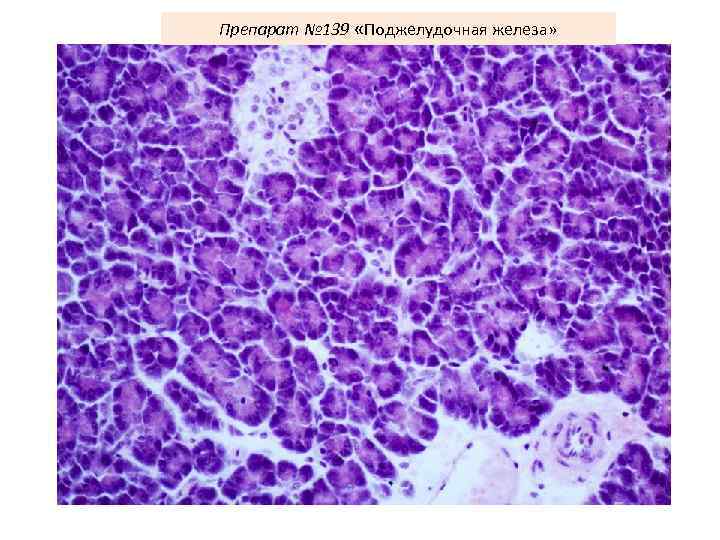

Препарат № 139 «Поджелудочная железа»